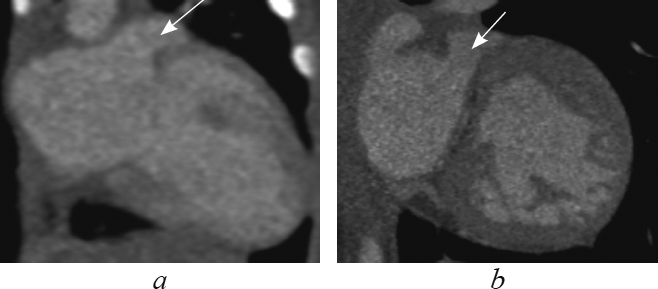

В данной статье приведены результаты анализа данных рентгеновской компьютерной томографии с внутривенным болюсным введением контрастного вещества детей с транспозицией и корригированной транспозицией магистральных артерий путем последовательного построения многоплоскостных реформаций, ориентированных на оси сердца. Из 148 детей со сложными врожденными пороками сердца и магистральных артерий транспозиция магистральных сосудов встречалась у 13 пациентов (в возрасте от 1 до 144 дней жизни; 9 — мужского пола, 4 — женского пола), корригированная транспозиция магистральных сосудов — у 4 пациентов (в возрасте от 6 мес. до 15 лет 6 мес.; 2 — мужского пола, 2 — женского пола). В статье подробно описаны анатомические характеристики, на основе которых определяется морфология каждой камеры сердца, и реформации, в которых они оцениваются. В статье приводится сравнительная характеристика структур сердца и магистральных артерий при транспозиции и корригированной транспозиции магистральных артерий в каждой отдельно взятой реформации, ориентированной на оси сердца. По результатам анализа последовательно построенных реформаций, ориентированных на оси сердца, указаны и проиллюстрированы характерные анатомические признаки транспозиции и корригированной транспозиции магистральных сосудов. Установлено, что из перечня предлагаемых реформаций, ориентированных на оси сердца, характерные анатомические признаки транспозиций достоверно определяются в следующих реформациях: по длинной оси приносящего тракта правого желудочка; левых камер сердца; приточных отделов желудочков; по короткой оси на уровне магистральных сосудов. Многоплоскостные реформации, ориентированные на оси сердца, на основе данных КТ-ангиокардиографии позволяют дать полную и точную анатомическую оценку сердца и магистральных сосудов, что важно при планировании оперативного вмешательства при врожденных пороках сердца.